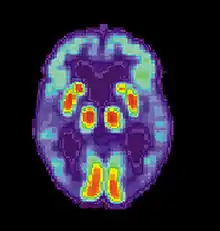

Obsessive compulsive disorder

Neuroimaging studies show that OCD patients perform considerably better on procedural memory tasks because of noticeable over-activation of the striatum brain structures, specifically the frontostriatal circuit. These studies suggest that procedural memory in OCD patients is unusually improved in the early learning stages of procedural memory.[69] Individuals with OCD do not perform significantly different on procedural working memory tasks than healthy controls.[27]